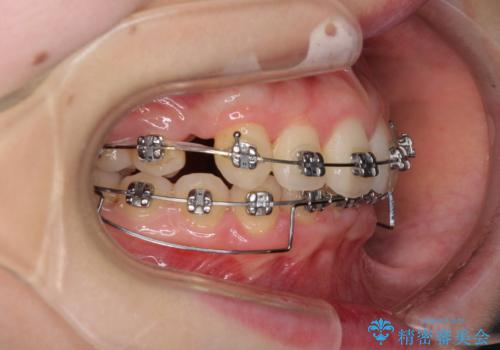

- 矯正装置

- メタルブラケット

奥歯の咬み合わせがなかなか定まらず、スペースが閉じるまでに時間がかかりましたが、最終的には正中を合わせることもできました。